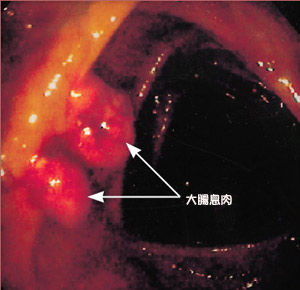

生活方式的不同還使城市與農村的癌症排序譜有所不同。在農村,發病率居高的是胃癌與食管癌;而在大城市卻是肺癌、直腸癌。上海市民中,大腸癌的發病率在各種癌症發病率的順序中已從第六位升至第四位,發病數淨增3倍,與近年來脂肪的進食增幅恰成正比。1998年,美國首次出現癌症死亡率下降趨勢,因為美國人更早更多地意識到了癌症與飲食習慣的關係,通過改變不良飲食習慣、戒菸及提高接種B肝疫苗覆蓋率,腫瘤發病就會逐步減少。